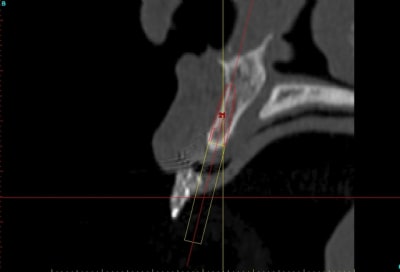

voilà, j'ai trouvé 5 mn...

le projet simplant est théorique, ça ne correspond pas à ce qui sera posé, c'était pour étude.

Fred à fait une séance d'ostéo-tension et 21 jours plus tard je me suis déplacé chez lui pour effectuer une deuxième séance, (nous avions adapté le protocole pour ce cas, 2 fois 21 jours au lieu de 40), afin de préparer le site et d'avoir une bonne connaissance du type d'os que nous allions trouver.